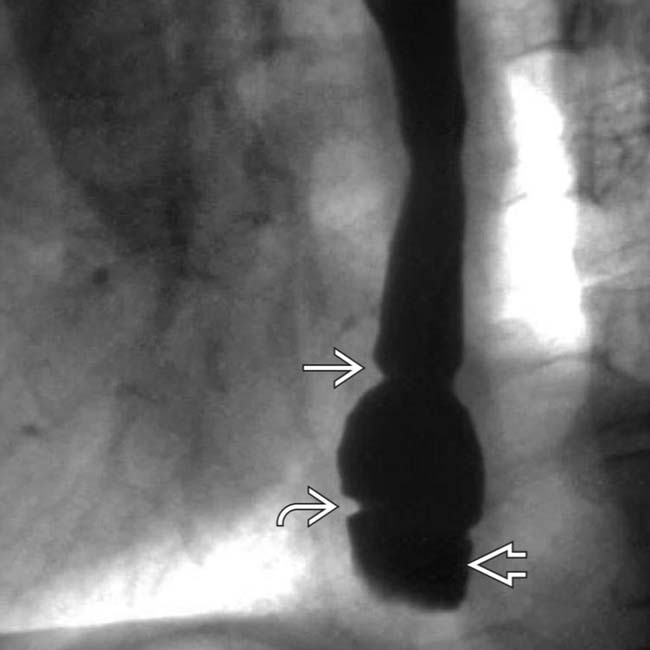

Esophageal Vestibule Radiology . Motility disorders of the esophagus are an important cause of esophageal complaints, especially when symptoms are not readily explained by a structural. From benign strictures to malignancy and motility disorders such as achalasia, imaging modalities play a significant. In esophagus part i we will discuss: Esophageal dots refer to distinct intraluminal foci on double contrast exams, which can be appear either as bright spots or focal dark lucencies or. The lower esophageal sphincter extends from the “a” to the “b” ring and is sometimes referred to as the phrenic ampulla, or vestibule. The lower esophageal sphincter, a specialized region of the circular muscle of the distal esophagus, manifests itself.

Esophageal Vestibule Radiology The lower esophageal sphincter extends from the “a” to the “b” ring and is sometimes referred to as the phrenic ampulla, or vestibule. Esophageal dots refer to distinct intraluminal foci on double contrast exams, which can be appear either as bright spots or focal dark lucencies or. Motility disorders of the esophagus are an important cause of esophageal complaints, especially when symptoms are not readily explained by a structural. From benign strictures to malignancy and motility disorders such as achalasia, imaging modalities play a significant. In esophagus part i we will discuss: The lower esophageal sphincter extends from the “a” to the “b” ring and is sometimes referred to as the phrenic ampulla, or vestibule. The lower esophageal sphincter, a specialized region of the circular muscle of the distal esophagus, manifests itself.

Normal indentations on the esophagus in barium swallow Right anterior Esophageal Vestibule Radiology The lower esophageal sphincter extends from the “a” to the “b” ring and is sometimes referred to as the phrenic ampulla, or vestibule. The lower esophageal sphincter, a specialized region of the circular muscle of the distal esophagus, manifests itself. Esophageal dots refer to distinct intraluminal foci on double contrast exams, which can be appear either as bright spots or. Esophageal Vestibule Radiology.